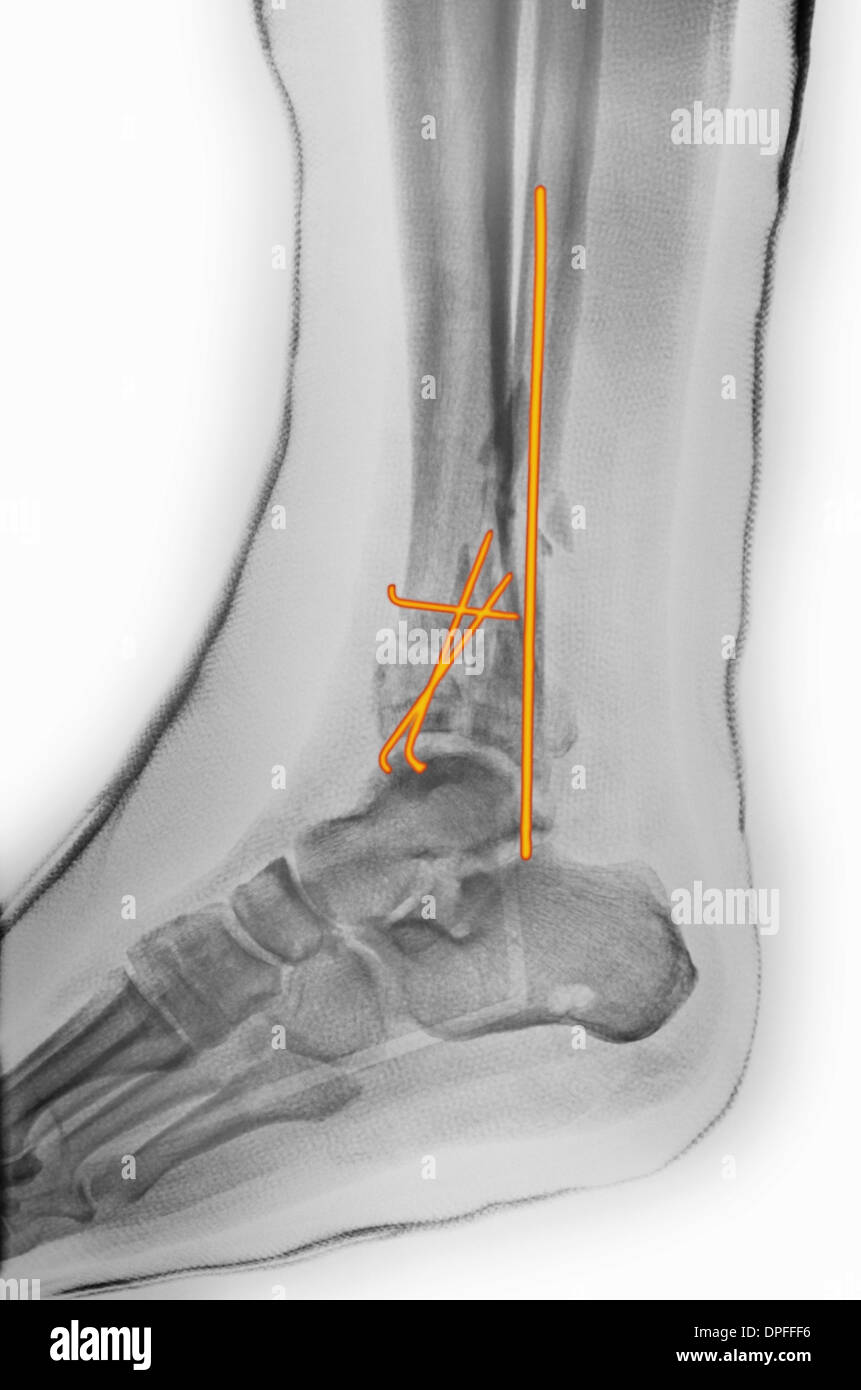

From www.alamy.com

xray of an ankle fracture after surgery Stock Photo Alamy Surgery After Fracture Open reduction and internal fixation (orif) is a type of surgery used to stabilize and heal a broken bone. A displaced or unstable fracture happens when the broken bone ends are out of alignment, requiring more complex treatment, often including surgery. Surgery for a hip fracture repairs a broken hip bone. It’s also known as open reduction and internal fixation.. Surgery After Fracture.